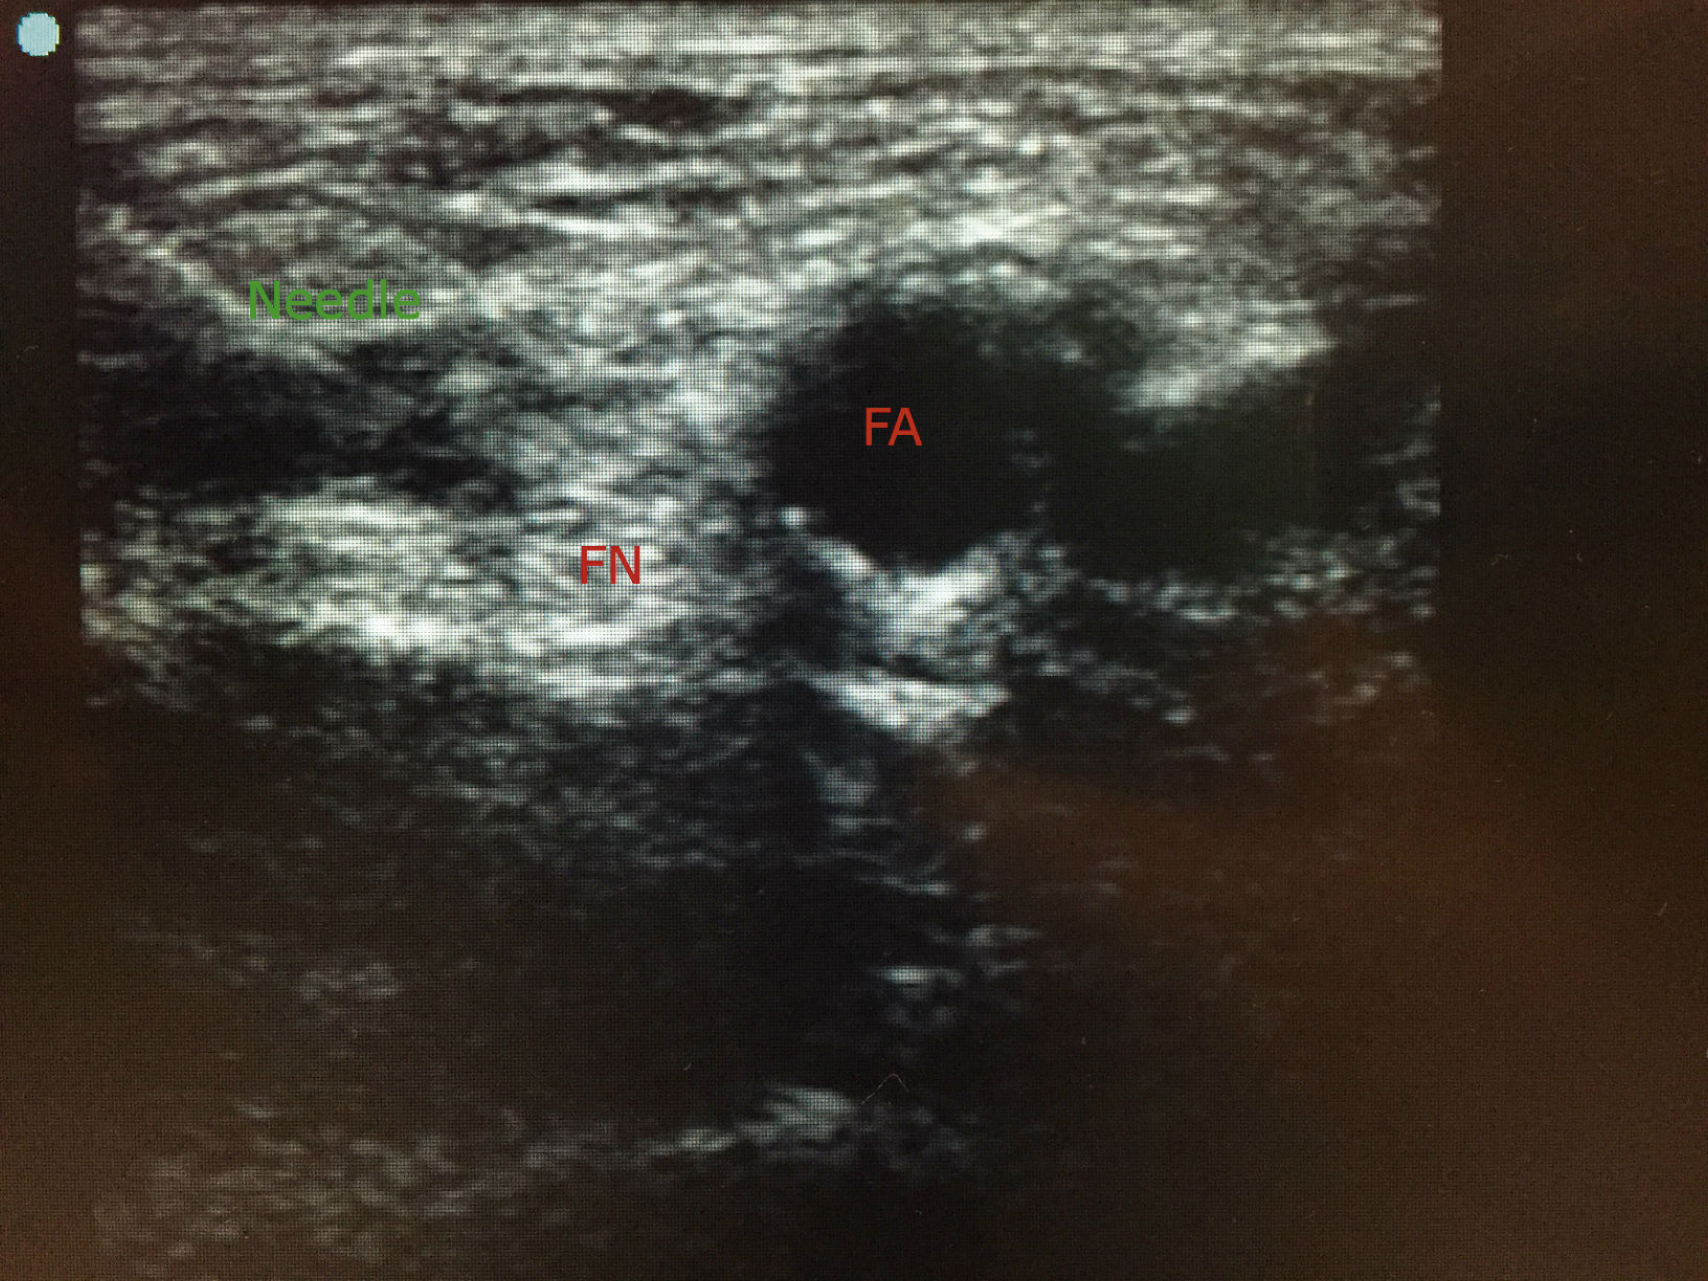

In the orthopedic and anesthetic literature, many “recipes” for FNB have been described. Traditional method is based on the description by Labat; using the inguinal ligament and a vertical line just lateral to the femoral artery as landmarks. In our center, we utilize a combined approach under ultrasound guidance and nerve-stimulation ( Figs. 50.1 and 50.2 ).

Ultrasound image showing the needle path (needle) to block the femoral nerve (FN). Blue dot marks the lateral side and femoral artery (FA) can be seen.